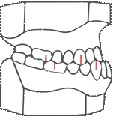

• studio delle radiografie della bocca (ortopantomografia) (Fig.3)

Fig.3. ortopantomografia